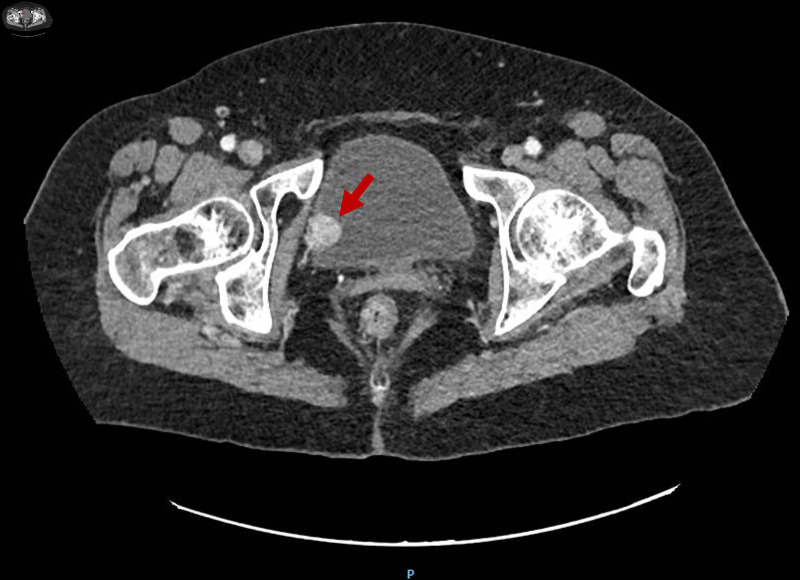

膀胱副神经节瘤占膀胱肿瘤的比例< 0.05%,目前报道的病例很少。由于临床和放射学的发现往往是非特异性的,许多病变被误诊直到手术,使患者暴露于可预防的围手术期儿茶酚胺危机。我们报告一个不寻常的情况下,77岁的妇女,其中17毫米膀胱副神经节瘤偶然发现影像学怀疑克罗恩病。患者完全无症状,儿茶酚胺水平正常。经尿道膀胱切除术(TURB)完全切除,6个月随访未发现复发。本病例说明膀胱副神经节瘤可发生在典型年龄范围之外,且无肾上腺素能症状,强调在鉴别诊断任何界限明确的高血管性膀胱肿块时需要考虑这一实体。早期识别有助于适当的围手术期计划和长期的多学科监测。我们讨论肿瘤的特点,管理和长期监测的重要性。

Bladder paraganglioma accounts for < 0.05% of all bladder tumors, and very few cases have been reported to date. Because clinical and radiological findings are often nonspecific, many lesions are misdiagnosed until surgery, exposing patients to preventable perioperative catecholamine crises. We report an unusual case of a 77-year-old woman, in whom a 17-mm bladder paraganglioma was discovered incidentally during imaging for suspected Crohn's disease. The patient was entirely asymptomatic and had normal catecholamine levels. Transurethral resection of the bladder (TURB) achieved complete excision, and no recurrence was detected at 6-month follow-up. This case illustrates that bladder paraganglioma can occur outside the typical age range and without adrenergic symptoms, emphasizing the need to consider this entity in the differential diagnosis of any well-circumscribed, hypervascular bladder mass. Early recognition enables appropriate perioperative planning and long-term multidisciplinary surveillance. We discuss the tumor's characteristics, management, and the importance of long-term surveillance.